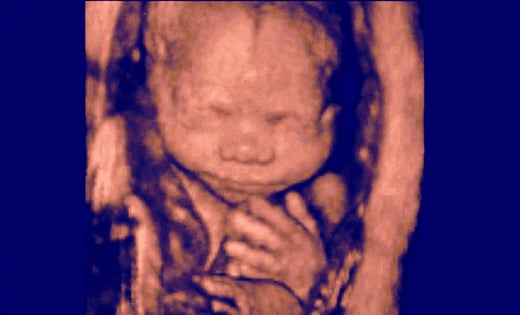

Pro-life laws blamed again